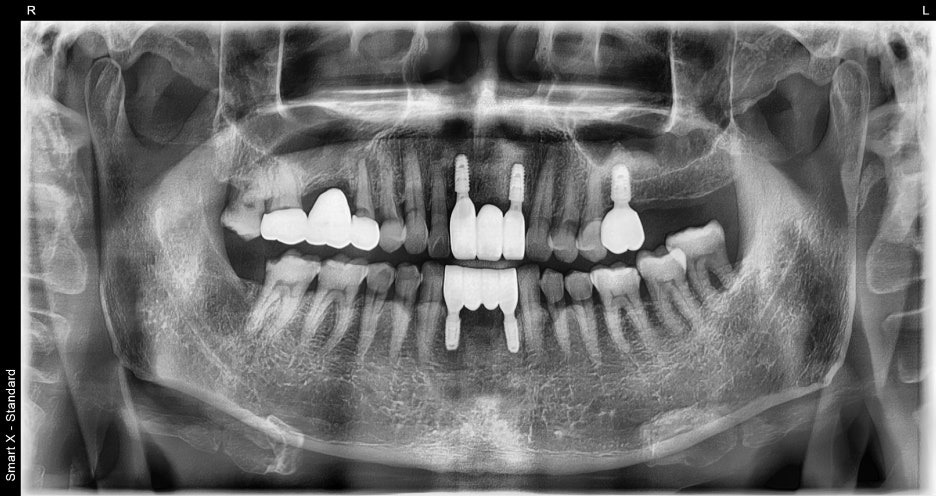

⑤ Prosthetic fabrication and placement

– Zirconia crowns were custom-made in our in-house laboratory.

– The front teeth were made in a natural and bright tone, while the molars were made with strength and durability in mind.

Treatment results

After completing treatment, the patient

regained his front teeth, which gave him more confidence when smiling,

and he was able to chew food comfortably again.

He was very satisfied.